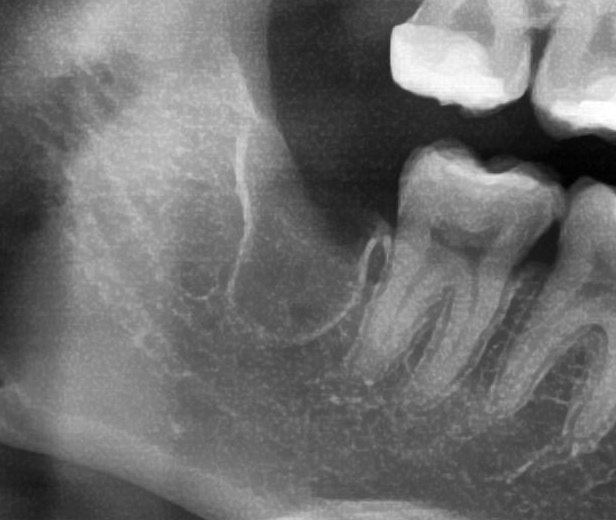

次にパノラマ写真を撮影してみると、手前の歯より低い位置でまっすぐに生えているのが確認できました。